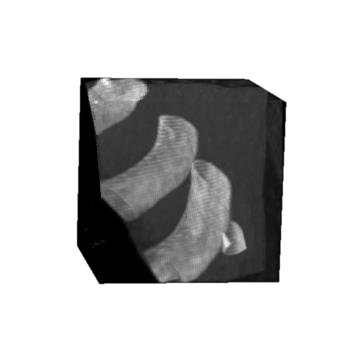

Rib fractures are a common and potentially severe injury that can be challenging and labor-intensive to detect in CT scans. While there have been efforts to address this field, the lack of large-scale annotated datasets and evaluation benchmarks has hindered the development and validation of deep learning algorithms. To address this issue, the RibFrac Challenge was introduced, providing a benchmark dataset of over 5,000 rib fractures from 660 CT scans, with voxel-level instance mask annotations and diagnosis labels for four clinical categories (buckle, nondisplaced, displaced, or segmental). The challenge includes two tracks: a detection (instance segmentation) track evaluated by an FROC-style metric and a classification track evaluated by an F1-style metric. During the MICCAI 2020 challenge period, 243 results were evaluated, and seven teams were invited to participate in the challenge summary. The analysis revealed that several top rib fracture detection solutions achieved performance comparable or even better than human experts. Nevertheless, the current rib fracture classification solutions are hardly clinically applicable, which can be an interesting area in the future. As an active benchmark and research resource, the data and online evaluation of the RibFrac Challenge are available at the challenge website. As an independent contribution, we have also extended our previous internal baseline by incorporating recent advancements in large-scale pretrained networks and point-based rib segmentation techniques. The resulting FracNet+ demonstrates competitive performance in rib fracture detection, which lays a foundation for further research and development in AI-assisted rib fracture detection and diagnosis.